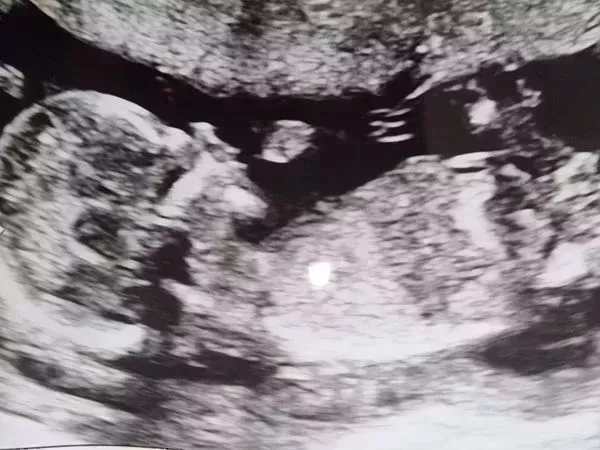

Zofia Fenrych se alegró mucho cuando vio a su bebé por nacer por primera vez en una ecografía rutinaria durante su 16ª semana de embarazo, el 5 de febrero de 2022.

"Se chupaba el dedo y se movía de un lado a otro", dijo la mujer de 40 años a Insider. Su pareja, Rob Velez, de 49 años, apenas pudo contener su emoción cuando miraron juntos la pantalla y vieron que estaban esperando una segunda hija.